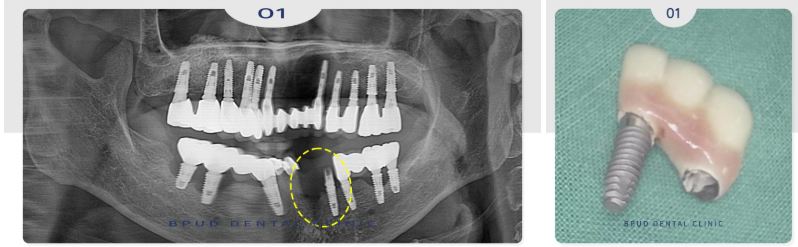

하지만 또 방치를 하시다가

한 달 후에는 결국 임플란트와 보철이

통째로 빠지셔서 내원해 주셨는데요.

자녀분들과 함께 내원하셔서

전체적인 설명을 충분히 드리고

제거 후 재식립을 진행하기로 하였습니다.

2024.08.12

수술 진행을 위해 잇몸을 열었을 때

잇몸에 완전히 묻혀 있어야 할

인공치근의 나사선들이 잇몸 위로

모두 드러나 있는 상태였습니다.

남겨서 사용할 수 있는 임플란트는

사용하기로 하셨지만 판단 결과

모두 다 제거하는 것이 맞다고 판단되어

식립 진행하였습니다.